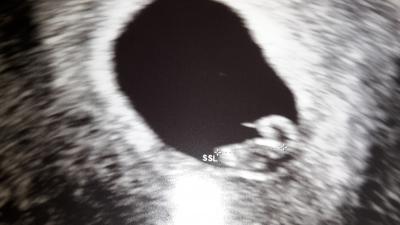

Hallo ihr lieben!!! Ich bin einfach nur Mega glücklich Krümel geht es gut! !! Jetzt heißt es 4 Wochen warten bis zum nächsten ultraschall. Hier noch ein Bild baby +Dottersack

Bild zu Herzchen schlägt fleißig - Forum für Januar - Mamis